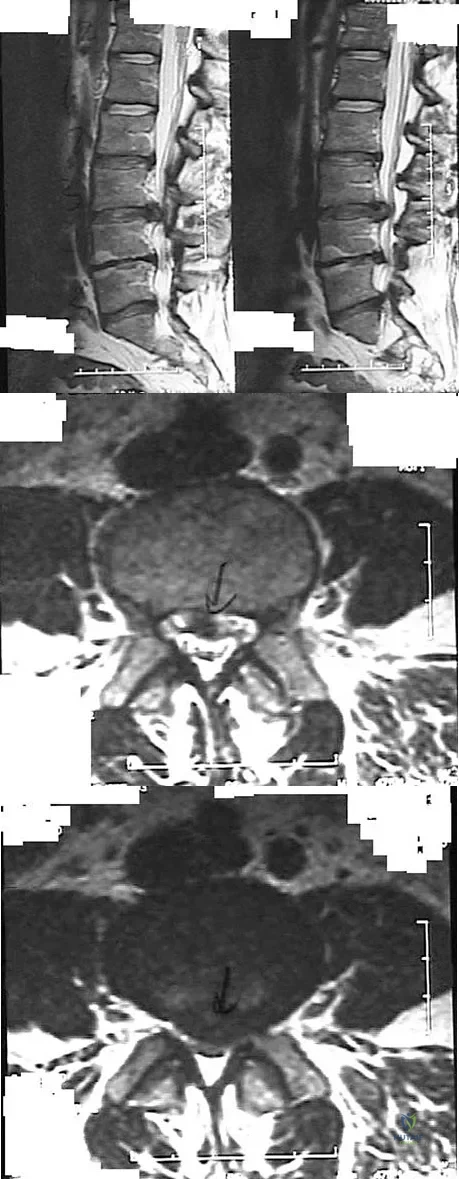

Question 39

Figures 28a through 28c show the MRI scans of a 30-year-old woman who weighs 290 lb and has low back and left leg pain. She also reports frequent urinary dribbling, which her gynecologist has advised her may be related to obesity. Examination will most likely reveal

Examination of a 34-year-old man who has had left leg pain for the past 6 weeks reveals minimal weakness of the left extensor hallucis longus and normal ankle jerk and patellar reflexes. Figure 33 shows an axial MRI scan of the L4-5 disk. Based on these findings, the MRI scan results are consistent with compression of the

Explanation